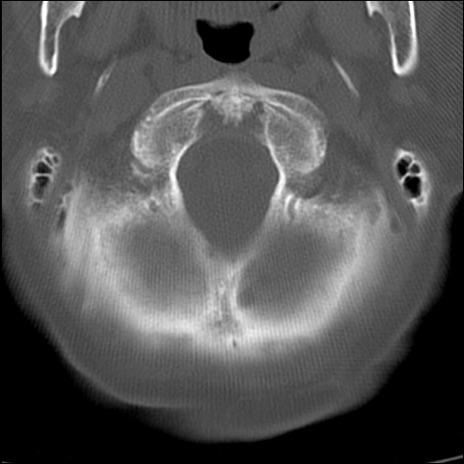

症例48 頚椎CT(横断像)

頚椎CT